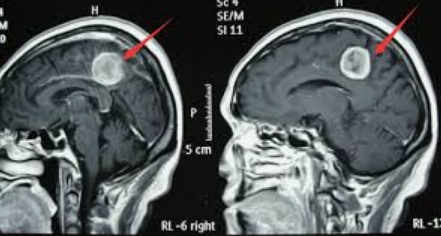

腦膜瘤怎么判斷是良性還是惡性?多數(shù)時候,單憑腦膜瘤的癥狀還不能完全確認腦膜瘤的性質(zhì),通過CT、MRI等影像學(xué)檢查,對于良、惡病現(xiàn)明顯的一般可以分辨。

腦膜瘤案例